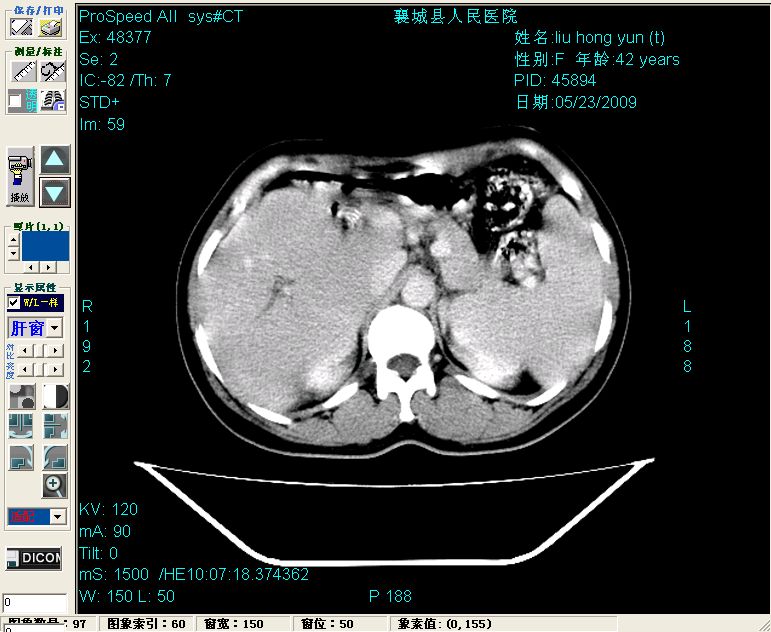

增强:

增强动脉期前述低密度区轻度早其强化,门脉期强化程度显著增高,延期扫描强化程度下降,但仍为相对高密度影

胰头部见结节状高密度影,其前方略可分辨扩强胆部管,平扫到增强始终有,但现在尚难与胃肠造影剂鉴别.

结合病史考虑,1现在引起黄疸体征的原因应该是胆总管胰段结石阻塞,建议局部胃肠造影剂排空后复查.

胆总管末端结石伴肝内胆管扩张合并结石!另:不除外合并胆系感染!

考虑:1、胆道结石伴肝内胆管扩张、积气;胆系感染!2、从平扫、增强片来看,不存在胆管肿瘤征象;3、提介建议:作为影像医师,在做一项检查之前应先熟悉临床医生的目的,象这个病例,检查前就不应喝高密度造影剂,而应充分喝好水就可,要不适得其反,反而较难判断胆总管下段是否有结石。

1)肝内胆管结石,胆总管末端结石伴肝内胆管扩张。2)肝左叶及肝右叶前段增强前后之异常表现,考虑炎性改变,不排除胆管细胞癌。

1)肝内胆管结石,胆总管末端结石伴肝内胆管扩张。2)肝左叶及肝右叶前段增强前后之异常表现,考虑炎性改变,不排除胆管细胞癌。3)脾大。